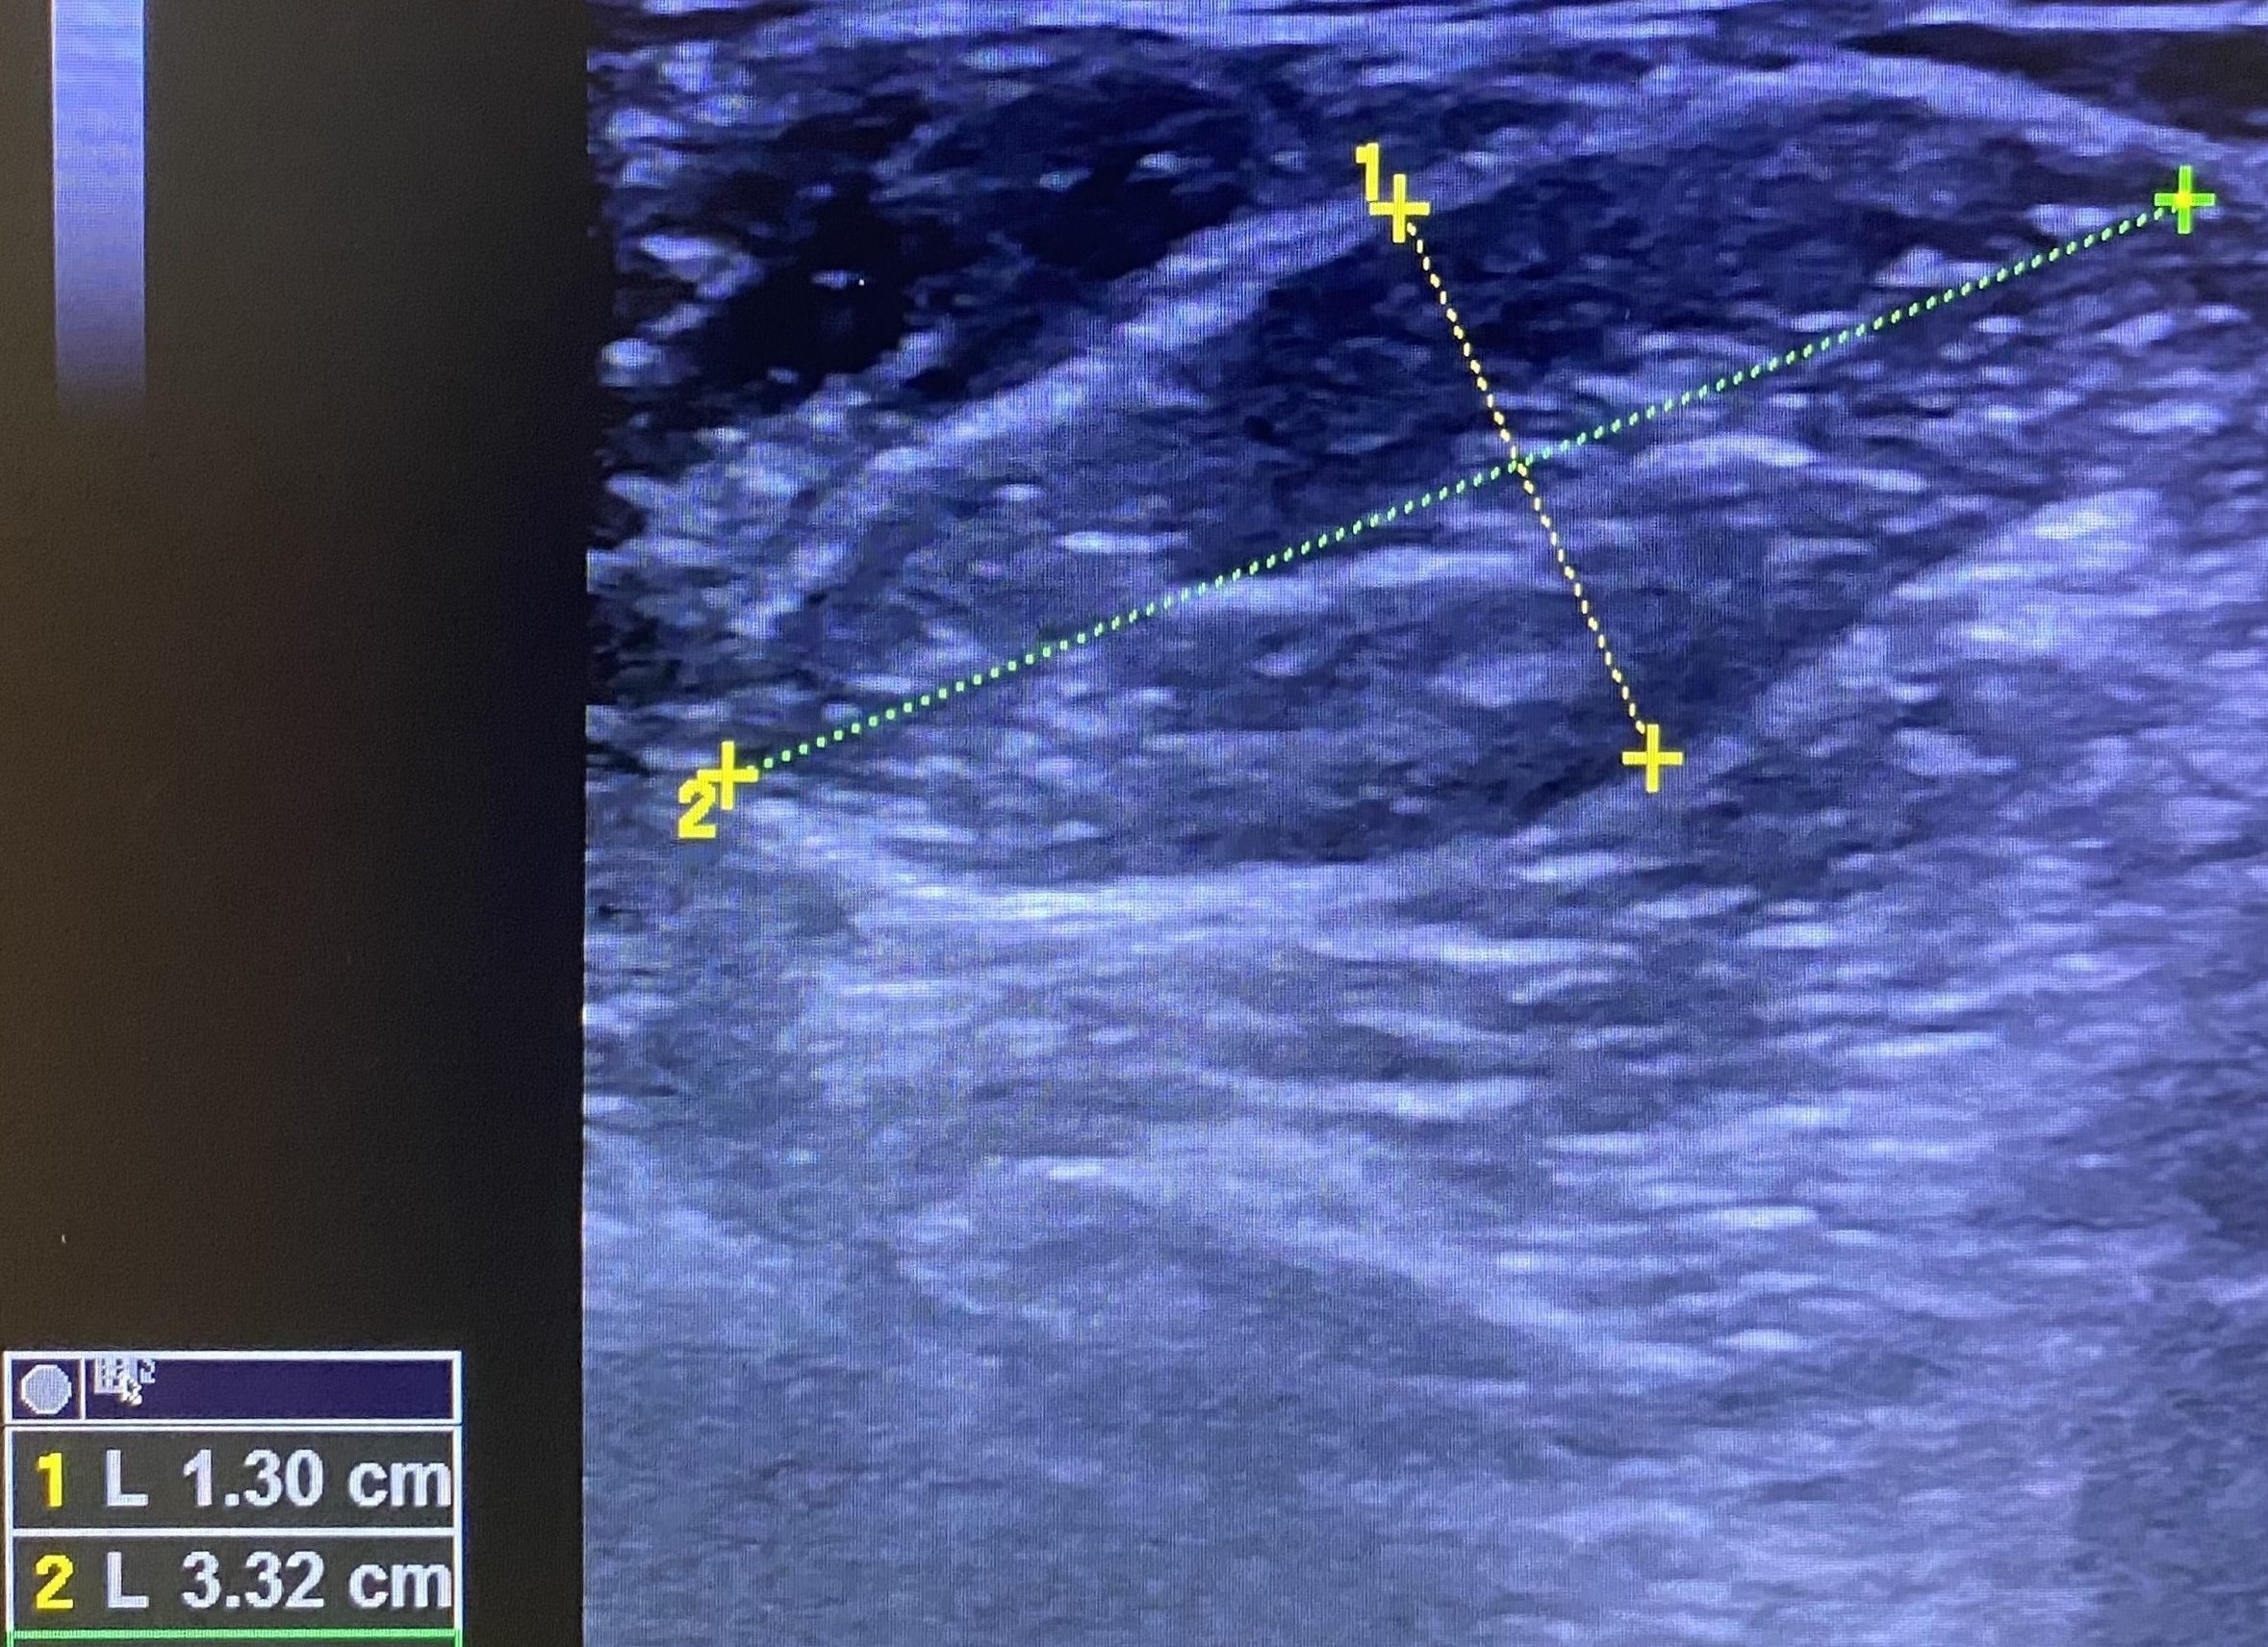

Se realiza una ecografía clínica en la consulta, objetivando múltiples adenopatías axilares izquierdas, la mayor con un tamaño de 2,85 x 1,74 cm. Se observa pérdida de hilio interior y aumento de diámetro transversal. El Doppler color es negativo.

Posteriormente, se solicita una ecografía reglada donde se confirman los hallazgos.